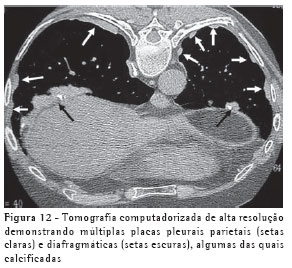

A TCAR é um método mais sensível e específico do que a radiografia. As placas pleurais são caracterizadas na TCAR como espessamentos pleurais focais, geralmente bilaterais, descontínuos, com bordas lisas, em platô, e por vezes com calcificações (Figura 12).(10-11)